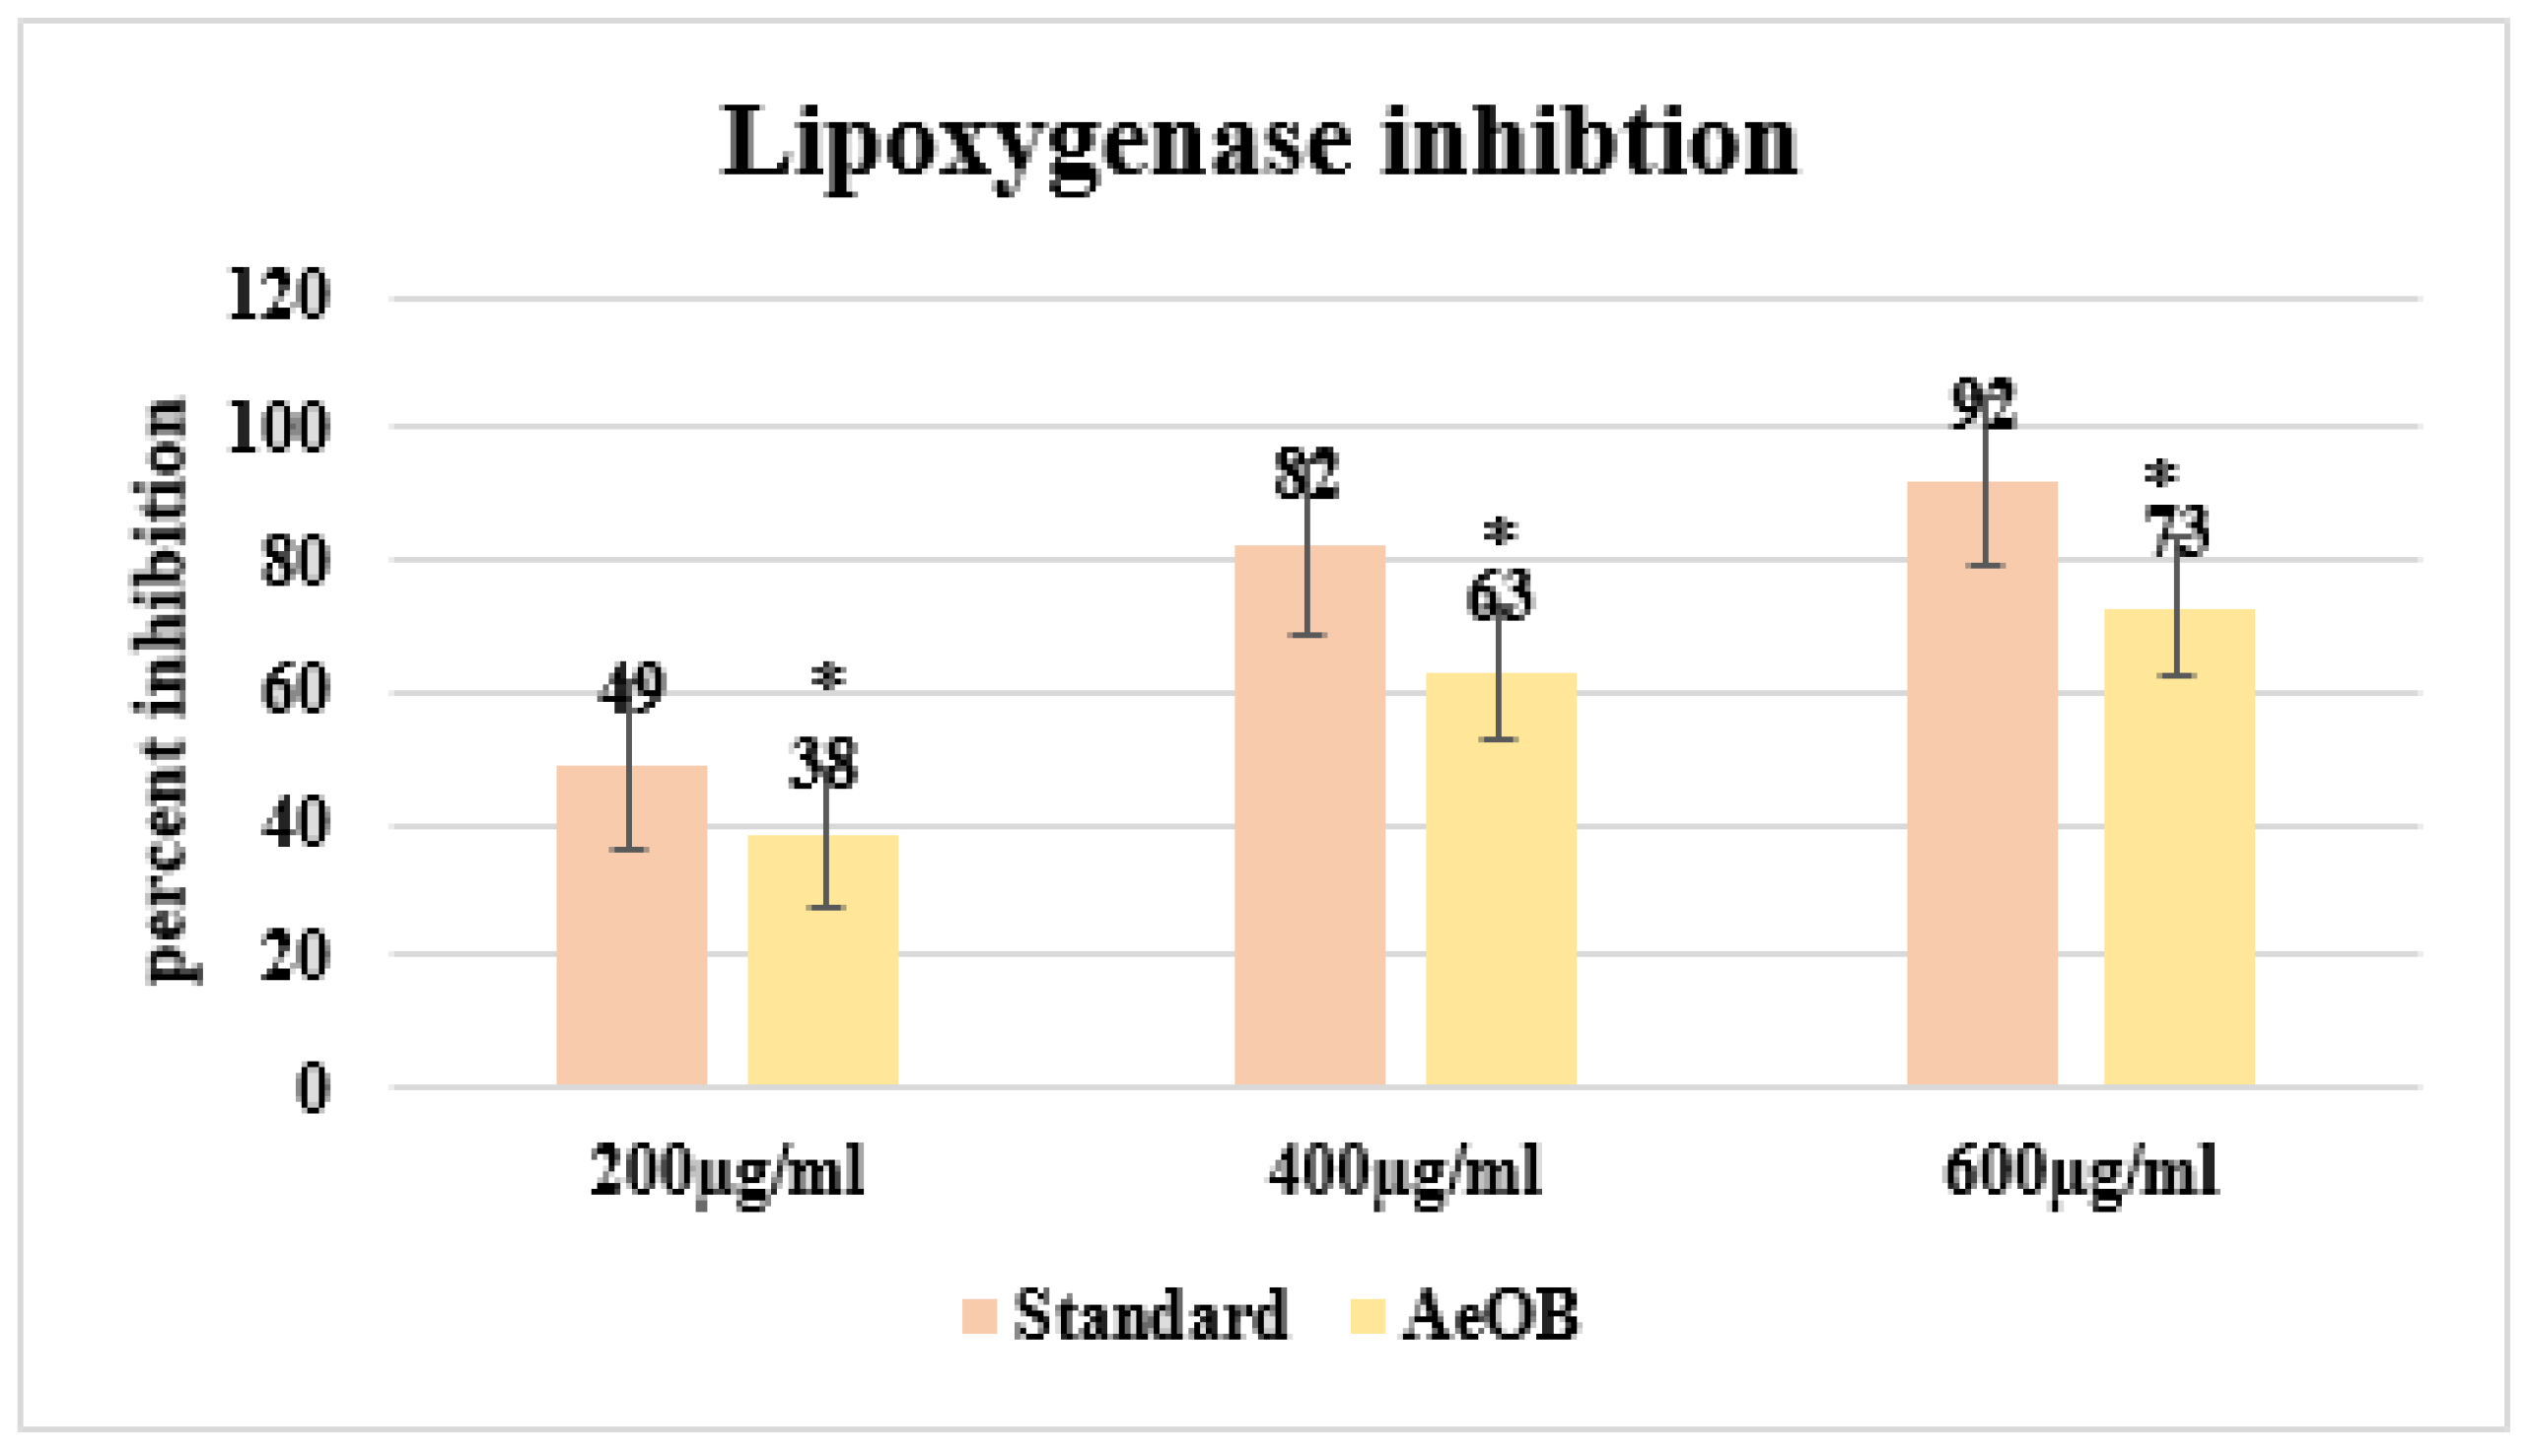

2.5.1. Lipoxygenase (LOX) Inhibitory Assay

4.7.1. Lipoxygenase (LOX) Inhibitory Assay